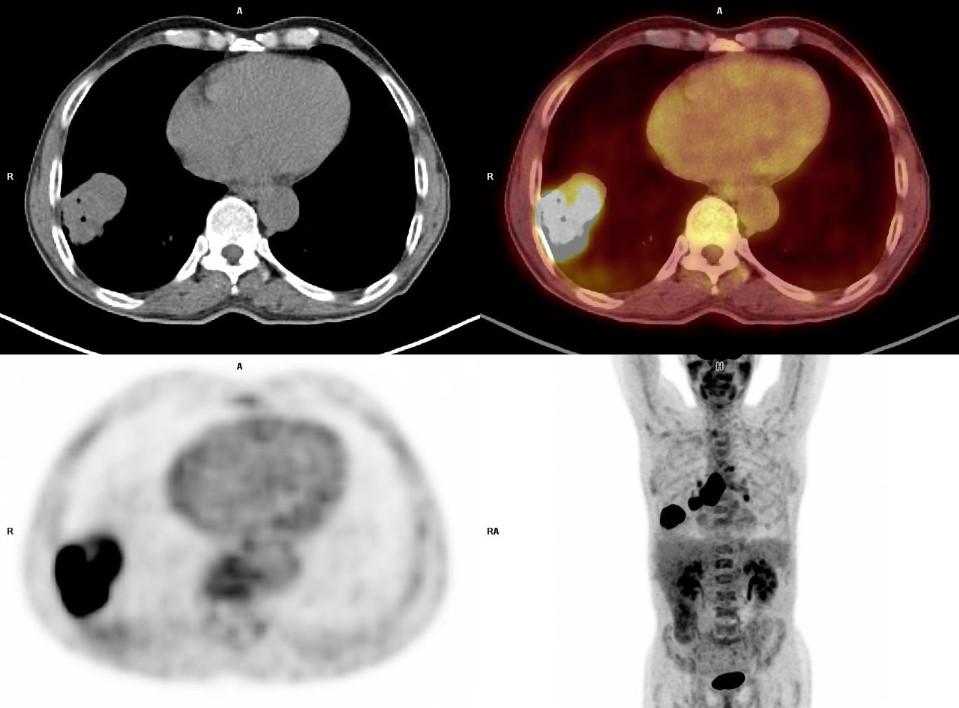

*66 years old male patient with larynx cancer.

Answer: Lung Cancer

66 years old male patient with larynx cancer. PET-CT showed a solid mass on right lung lower lobe and subcarinal enlarged lymph node with high FDG uptake. Histopathology revealed squamous cell cancer.